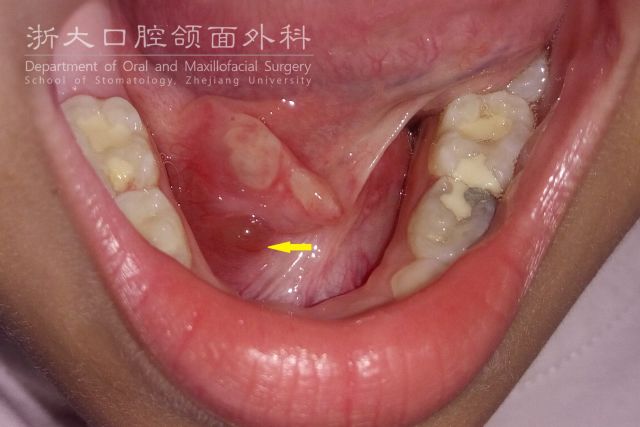

向左滑动可查看舌前腺黏液囊肿图片

其实,这是临床上常见的一类小唾液腺黏液囊肿——舌前腺黏液囊肿,约占口腔黏液囊肿的10-15%,多发于青少年与儿童。

舌前腺囊肿是发生在舌前腺的黏液囊肿,是一种良性病变,多发于青少年与儿童。舌前腺囊肿多是由于舌体运动而受下前牙摩擦,或是由于自觉或不自觉的咬舌动作导致外伤,从而造成导管破裂黏液外渗引发囊肿;也有可能是由鱼刺、骨渣等食物来源的损伤所致。

囊肿常呈半透明的小泡,状似水泡,可呈蓝紫色或粉红色,逐渐增大,大多为黄豆至樱桃大小,质地软而有弹性。无痛,但囊肿变大后可影响进食与发音。囊肿易被咬破,流出蛋清样透明黏稠液体,此时囊肿变小或消失。易复发,反复破损后可表现为较厚的白色瘢痕状突起,囊肿透明度降低。另外,囊肿有时也可能长得像血管病变、化脓性肉芽肿、息肉、乳头状瘤。